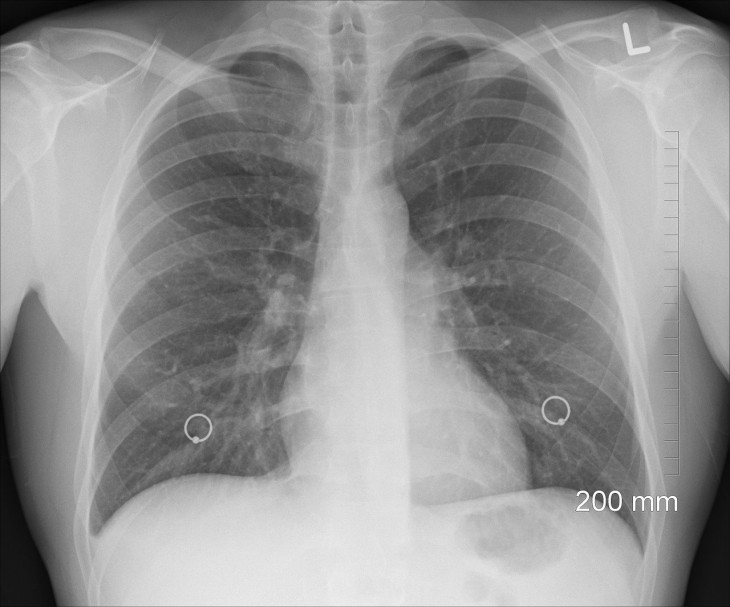

В журнале сообщают, что изучение данных в данном направлении напрямую касается коронавирусной инфекции, пневмонии и рака легких.

Также исследования помогут бороться с астмой и болезнью ХОБЛ.